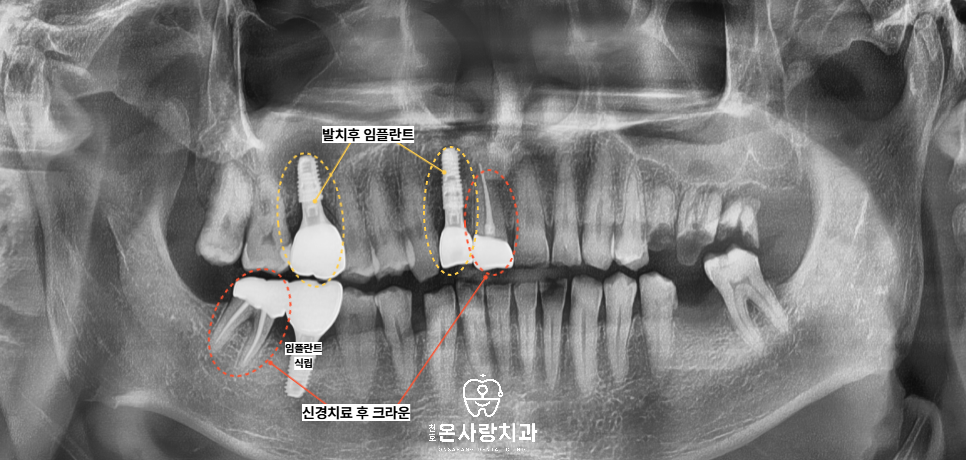

이번에 천호역치과 병원을 찾아주신

환자분께서는 이미 구강내

다양한 문제점을 가지고 계셨습니다.

충치로 인한 치아의

손상이 극심해서

거의 치아의 절반이상

남지 않은 치아들은

발치를 한 뒤 임플란트를

하기로 결정하였습니다.

그리고 손상되었긴 하지만,

신경치료를 하고 크라운으로

마무리를 해서 보존하는 것이

더 유리한 치아도 있었습니다.

마지막으로 이미 상실되어있던 부위에는

임플란트를 식립하여서 저작기능을

회복하기로 하였습니다.

오른쪽의 문제점들은

모두 적절한 치료를

결정하여 마무리를

완료하였습니다.